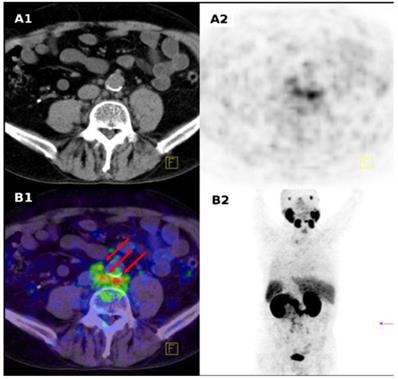

Somatostatin receptor imaging

The expression of SSTRs has been found in neuroendocrine tumours, small cell lung cancer, renal cell carcinoma, malignant lymphoma, breast cancer, and prostate cancer. PET-CT using somatostatin ligand analogues labelled with 68Ga has become a new golden standard in imaging of NETs with specificity and sensitivity well above 90% and advantages over conventional radiologic and scintigraphic imaging [14, 146-149]. It is the most pronounced example of theranostics [6, 7, 150].

Extensive basic research has been conducted on the development and biological validation of analogues varied in peptide sequence, size and number of peptide rings, chelator (DFO, DTPA, DOTA, NOTA, and their derivatives) and radiometal (Ga, Y, Tc, In, Lu) type. Their receptor binding affinity, internalization and biodistribution have been shown to be dependent on the chemical modifications [2]. Fast tumour localization, blood clearance, and renal excretion are typical characteristics of clinically used [68Ga]Ga-DOTA-TATE, [68Ga]Ga-DOTA-TOC, [68Ga]Ga-DOTA-1-Nal3-octreotide ([68Ga]Ga-DOTA-NOC). Structure activity relation studies allowed fine tuning for the agent properties such as receptor affinity, in vivo stability, biodistribution, pharmacokinetics, excretion pathway, and kidney uptake, and pharmacological activity [138, 151-155].

The feasibility of quantitation of SSTR density has been demonstrated both preclinically [25, 160] and clinically [24] using [68Ga]Ga-DOTA-TOC. Although a ten-fold higher affinity for the SSTR2 had been demonstrated for DOTA-TATE as compared to DOTA-TOC in vitro in transfected cell cultures [161], no statistically significant difference between [68Ga]Ga-DOTA-TOC and [68Ga]Ga-DOTA-TATE uptake could be observed in vitro in monkey brain tissue sections or in vivo in rat organs expressing SSTRs ( pituitary, adrenal, pancreas) [103]. Moreover, clinical study involving 40 patients did not verify the 10-fold higher affinity for the SSTR2 of [68Ga]Ga-DOTA-TATE, on the contrary, standardized uptake value (SUVmax) of [68Ga]Ga-DOTA-TOC tented to be higher [162]. Another aspect investigated preclinically is the influence of treatment with octreotide and interferon-a (IFNa) used for biotherapy of NETs on the uptake of [68Ga]Ga-DOTA-TATE. The exposure of the animals to the cold octreotide did not enhance the uptake of the tracer while IFNa did, however the mechanism of the observation was not clear [163, 164]. Gene therapy protocols were optimized on the basis of in vivo imaging ([68Ga]Ga-DOTA-TATE) of gene expression and quantitative monitoring of gene transfer [165].

[68Ga]Ga-DOTA-TOC (27), [68Ga]Ga-DOTA-TATE (28) and [68Ga]Ga-DOTA-NOC (29) (Figure 6) are the most commonly used analogues in clinical studies [2, 166, 167]. Their pharmacokinetics, blood clearance and target localization rate are compatible with half-life of 68Ga. Renal excretion, short scanning time, high sensitivity and resolution assure high contrast and quality images over organs of interest as well as accurate quantitation. Relatively low radiation dose is one more advantage that should be mentioned. They served for diagnosis, staging, prognosis, therapy selection and response monitoring of NETs and other types of cancers and diseases. [68Ga]Ga-DOTA-TATE was compared with [68Ga]Ga-DOTA-NOC in 20 patients in terms of detection rate and SUVs [168]. The agents had comparable diagnostic accuracy with higher SUVmax for the former. One more analogue, [68Ga]Ga-DOTA-2-Nal, Tyr3, ThrNH28-octreotide (DOTA-lanreotide, DOTA-LAN) was successfully used for lung and thyroid tumour detection [169].

The individualized diagnosis has been practiced in the selection of patients for PRRT, target definition for fractionated stereotactic radiotherapy (FSRT) planning, target volume delineation for intensity modulated radiotherapy [170-174]. The diagnosis on the cellular and molecular level and determination of the disease associated biomarkers provides basis for the treatment optimization and efficacy for a particular patient [175]. The personalized therapy planning necessity was demonstrated in retrospective study of ten patients examined with [68Ga]Ga-DOTA-TATE [176]. It was concluded that the radiotherapeutical dose should be determined by the tumour burden since the latter influences the radioactivity distribution to the healthy organs, and in particular the higher burden decreases the radiation accumulation in the kidney. The starting point of PRRT after preceding cold octreotide therapy in patients with NETs could be determined [177]. These imaging agents improved the detection rate and diagnostic accuracy [178, 179]. They were used for therapy planning and monitoring response to treatment [180], as well as influenced and changed the therapeutic course [181-184].